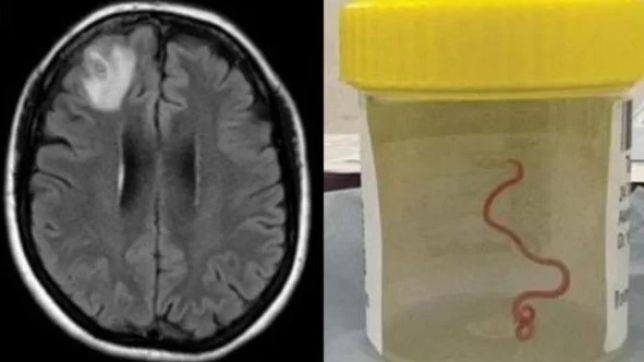

Em um caso inédito e inusitado, médicos descobriram que uma mulher australiana de 64 anos com problemas de memória tinha, na verdade, um verme de oito centímetros, ainda vivo, alocado em seu cérebro.

Segundo os responsáveis pelo atendimento, este é o primeiro caso de parasita do tipo Ophidascaris robertsi no cérebro humano.

Vermes desta espécie normalmente são parasitas de cobras píton — os humanos geralmente são hospedeiros ocasionais de suas larvas.

No entanto, neste caso, o animal acabou indo parar no cérebro da mulher.